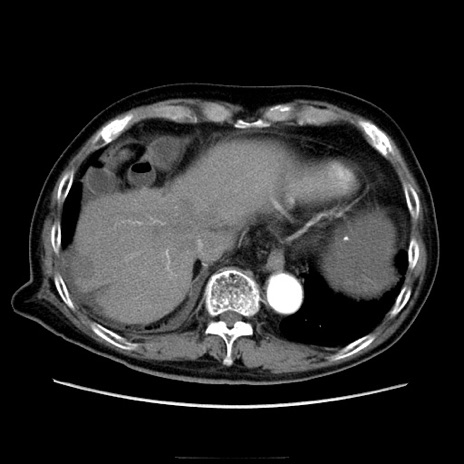

症例21(横断像)

【症例】70歳代男性

【主訴】腹痛

【現病歴】肝硬変・肝細胞癌にてかかりつけの方。約9時間前に食後より腹痛出現。症状が徐々に増悪し、嘔吐出現したため来院。

【既往歴】肝硬変、肝細胞癌(RFA、TACE後)

【身体所見】意識清明、表情苦悶様、BT 36℃、BP 129/78mmHg、P 88bpm、SpO2 97%(RA)、右上腹部から心窩部にかけて圧痛あり、反跳痛なし、筋性防御あり。

【データ】WBC 5800、CRP 0.16